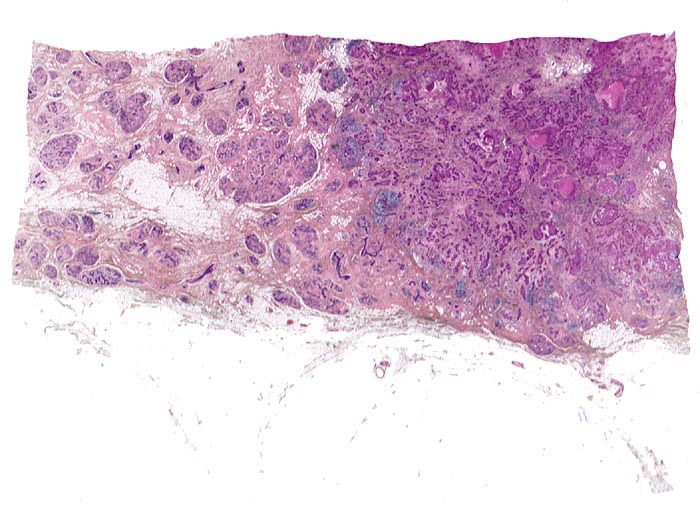

Links im Bild normale Drüsenläppchen. Rechts das Karzinom ohne erkennbare Läppchenstruktur mit Entzündungsinfiltraten im Bereich der Invasionsfront und herdförmigen Tumornekrosen.

Makroskopisch: derber weisser Herd von 2.2cm Durchmesser im oberen äusseren Quadranten.

Die Patientin hatte bei der Selbstuntersuchung einen harten Knoten in der rechten Mamma palpiert. Nach dem Nachweis von Karzinomzellen in der Feinnadelpunktion wurde eine Lumpektomie durchgeführt. Die intraoperative Schnellschnittuntersuchung ergab tumorfreie Resektionsränder.